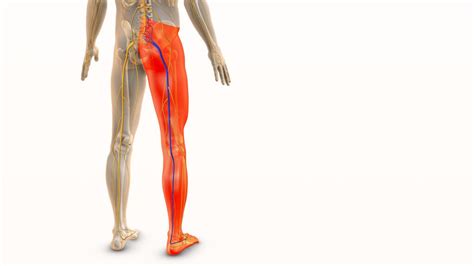

Redek zaplet je sklop bolezenskih znakov, ki se pojavijo zaradi pritiska vnete hrbtenice na snop živcev, ki potekajo v hrbtenjačnem kanalu pod hrbtenjačo. Huda vnetja oči ali živčevja je treba zdraviti s prednizonom ali drugim kortikosteroidom. Kosti hrbtenice ščitijo hrbtenjačo in hrbtenjačne živce. Zdrava hrbtenica je kot prožna vzmet, ki prenese mnogo večje obremenitve kot zakostenela in negibna hrbtenica bolnikov z ankilozirajočim spondilitisom, ki je zaradi osteoporoze tudi krhka. Že manjše nezgode lahko povzročijo njen zlom. Najpogosteje se zlomi posamezno vretence v spodnjem delu vratne hrbtenice. Zlom in premik kostnih odlomkov lahko povzroči ukleščenje hrbteničnih živcev in hrbtenjače. Pojavijo se lahko nevrološki znaki, ki so odvisni od mesta prizadetosti hrbtenjače. Ti znaki so: izguba občutka za dotik in zmanjšanje moči v rokah ali/in nogah ter težave pri nadzorovanju odvajanja vode in blata. Če se pri posamezniku pojavi katera od opisanih težav, mora nemudoma poiskati zdravniško pomoč, tudi če je bila poškodba na videz nepomembna.